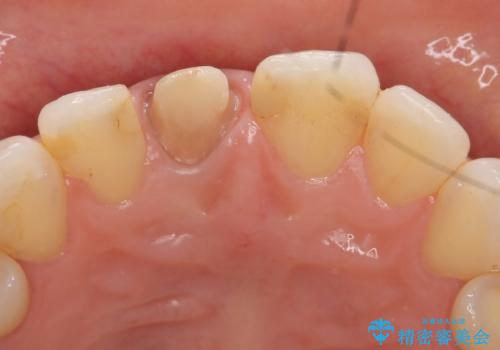

- 右上1番目の歯の変色が気になると来院された方の症例です。

検査の結果、右上1の歯は失活(歯の神経が死んでいること)していたため根管治療を行いました。

その後オールセラミッククラウン(スペシャル)による補綴を行いました。

- オールセラミッククラウン(スペシャル)…¥130,000 ファイバーコア…¥20,000費用は治療当時の料金となります